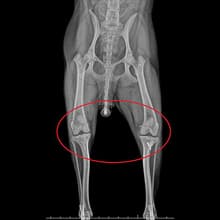

엑스레이2살 비숑프리제 : 슬개골탈구 수술

2살 비숑프리제가 옥길아라동물치료센터에 내원했습니다. 처음 내원할 때, 아이가 잘 걷지 않으려고 해서 병원에 내원해주신 경우입니다. 정확한 확인을 위해 정형 검사와 영상 검사를 진행하였습니다. 꼼꼼한 검사 결과 우측 슬개골 탈구3기와 좌측 슬개골 탈구 2기로 진단되었습니다. 엑스레이 검사 상으로 양측 슬개골이 내측으로 변위되었고, 우측의 변위가 더 심했습니다. 보행에 큰 불편함이 확인된 상태로 수술적 치료가 필요한 상황이었습니다. 수술은 증상에 따라 다른 수술 방법이 적용됩니다. 옥길아라동물의료센터 의료진은 정밀한 수술과 예후 관찰을 진행하였습니다. 양측 대퇴골 활차구 성형과 슬개골 탈구 3기에 해당하는 우측은 경골 조면 이식술을 병행 적용키로 결정하여 수술을 진행하였습니다. 수술 경험이 풍부한 외과 전담 선생님과 전문 의료진이 아이의 수술을 전담 진행하였고, 수술 후에는 빠른 회복을 재활치료를 진행해 주었습니다. 수술 후 2일차부터 염증 수치는 안정화되었고, 3일차 부터 잘 걷게 되어 무사히 보호자님께 인계되었습니다.